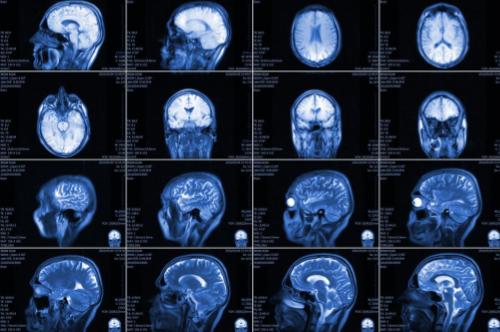

A Phase 3, open-label, randomized 2-arm study comparing the clinical efficacy and safety of niraparib with temozolomide in adult participants with newly-diagnosed, MGMT unmethylated glioblastoma

This study compares treatment with niraparib to temozolomide in adult participants who have newly-diagnosed, MGMT unmethylated glioblastoma.

Clinics and Surgery Center (CSC), Brain Tumor, GBM, Glioblastoma